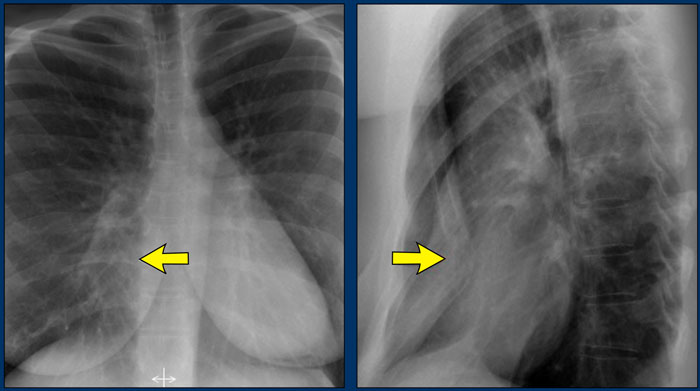

Hidden Areas (3): Pneumonia Below the Diaphragm

In this case, a pneumonia was primarily located below the right diaphragmatic dome (yellow arrow), within the posterior basal segment of the right lower lobe.

• On the lateral view, there is an increase in opacity over the lower thoracic vertebrae, indicating lower lobe consolidation (arrow).

• Again, image magnification may be necessary for adequate assessment.

Hidden Areas (6): Subtle Consolidation Behind the Heart

In another example, there is a subtle left lower lobe consolidation localized to the retrocardiac area—again, a commonly overlooked region.

• On the lateral view, the pathology manifests as increased density over the lower thoracic vertebrae.

• Consistent with posterior lower lobe pneumonia.